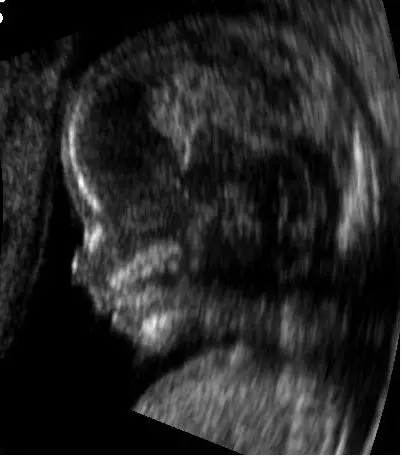

Također, obavljaju i color doppler test, te imaju i uređaj za 4D ultrazvuk, nude i papa testove, bakteriološki brisevi te vaginalne pesare, spirala. Ordinacija nudi i Harmony Prenatal test.